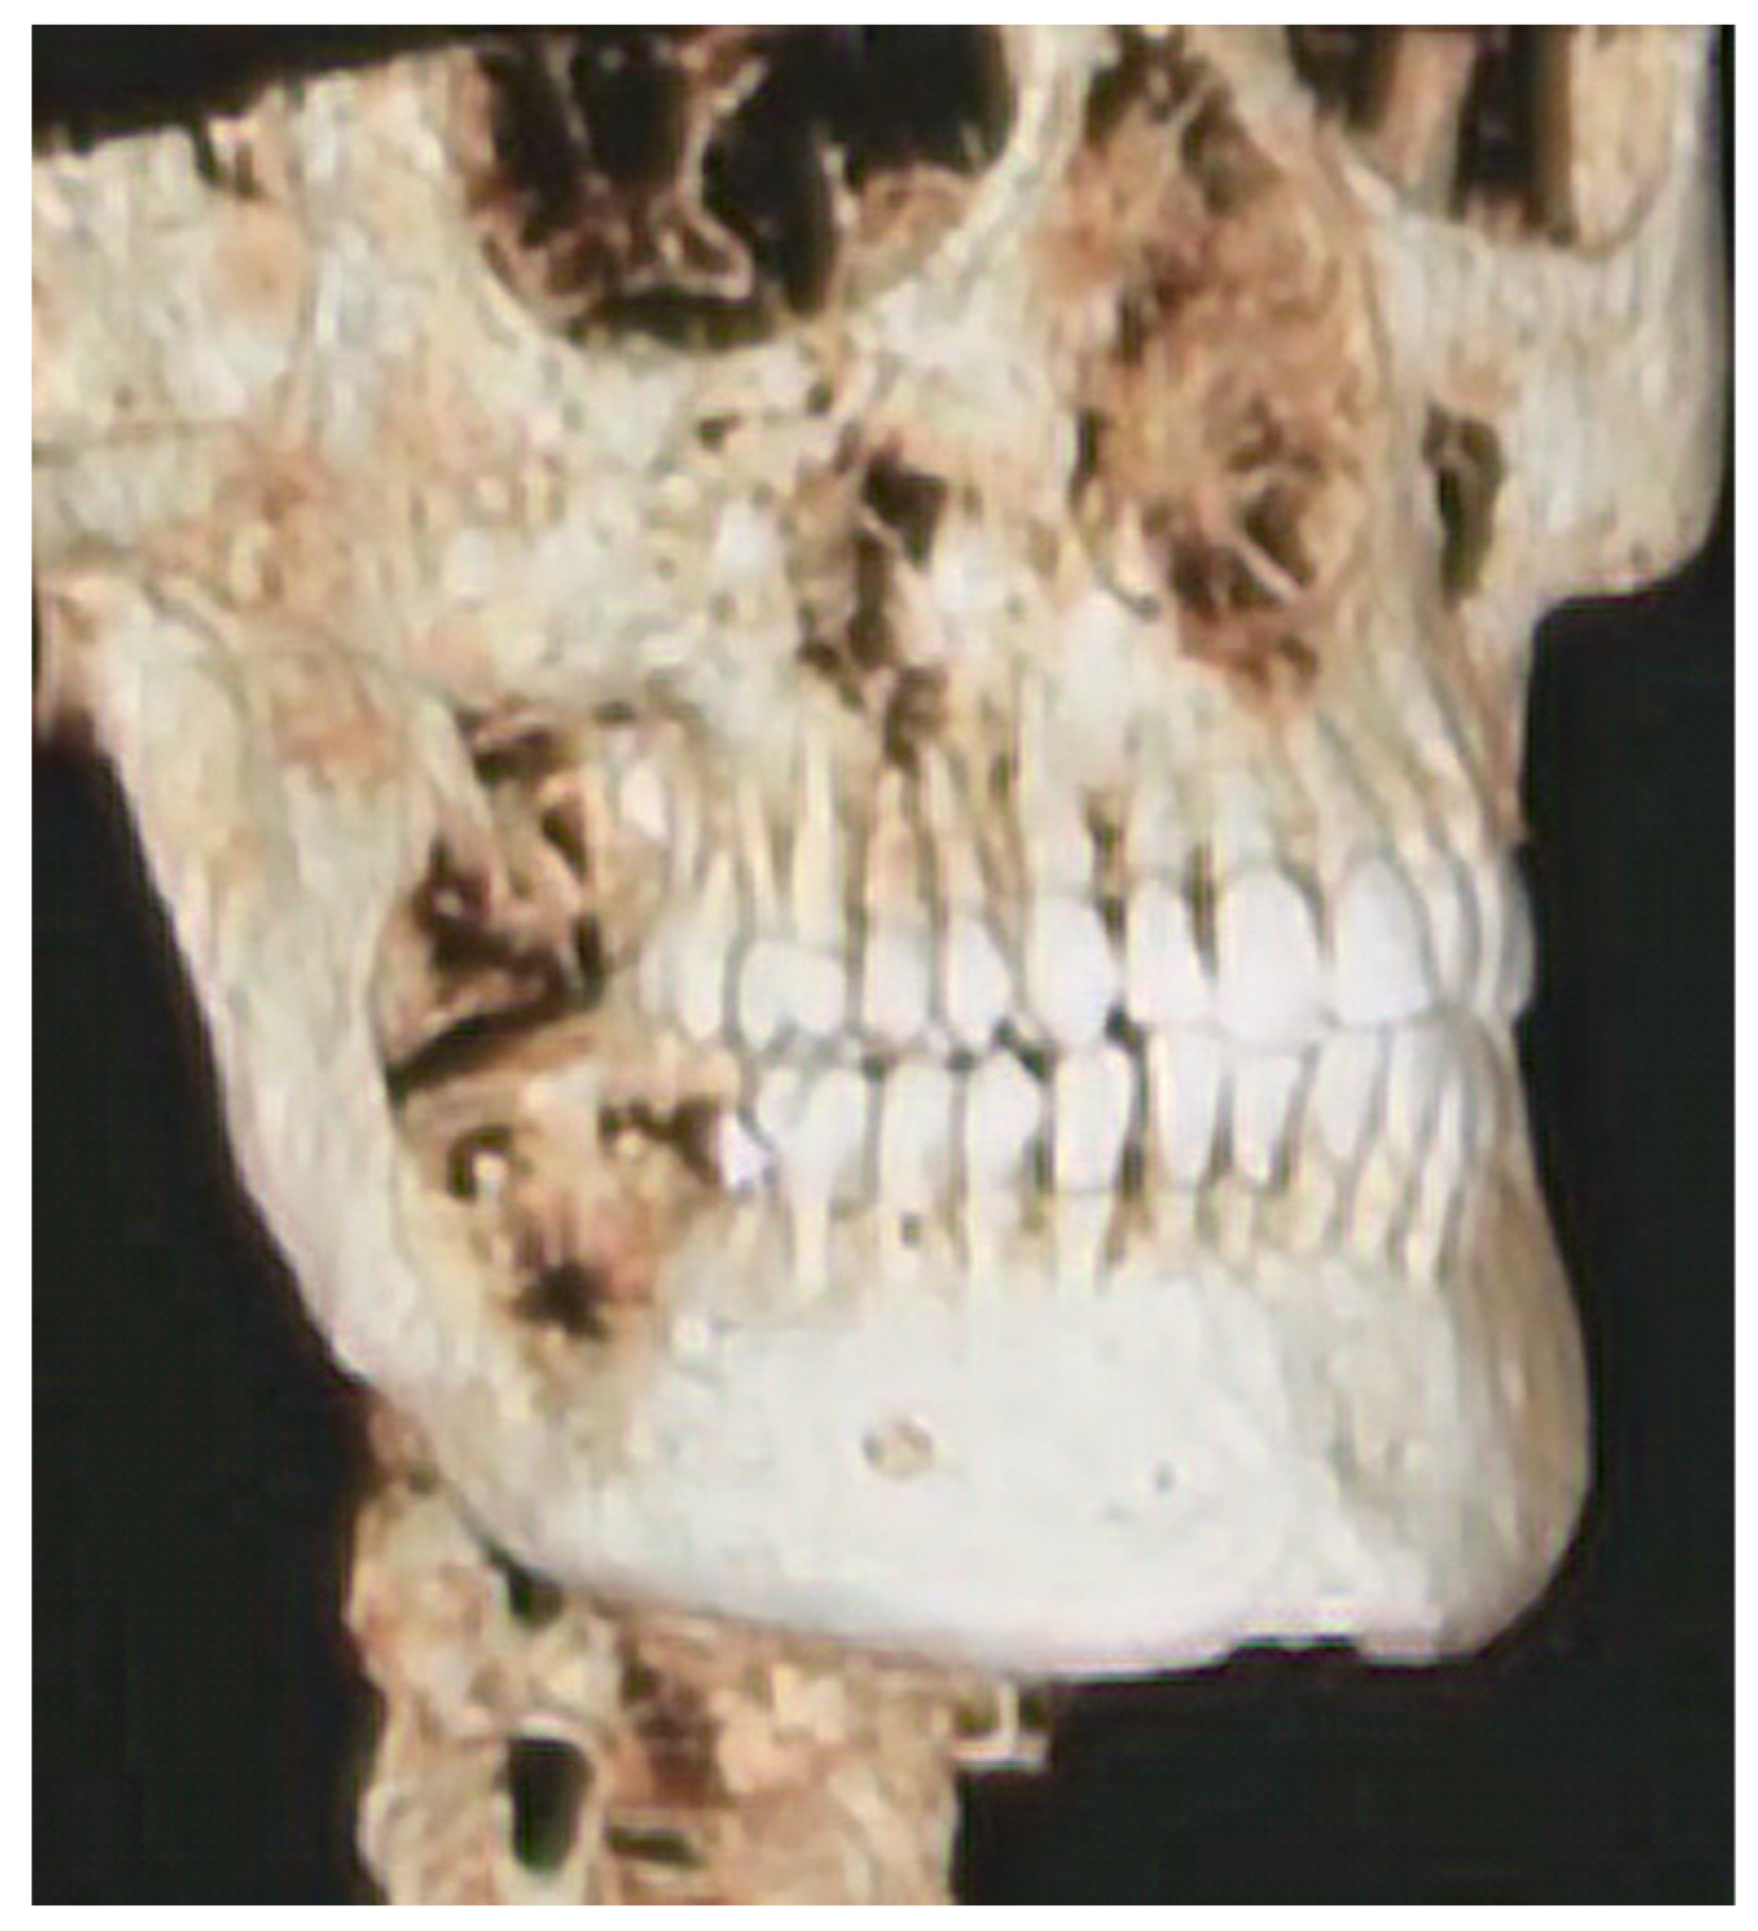

2.1. Patient #1

2.2. Design Case #1